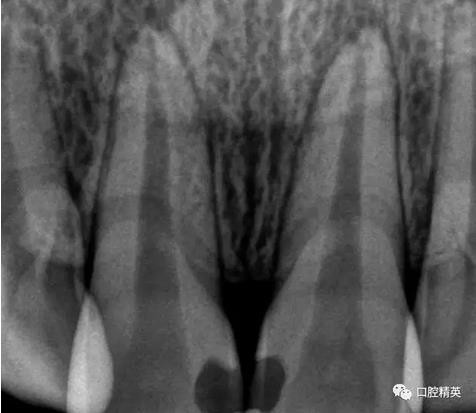

檢查:11,21近中鄰面可見樹脂類充填體,兩牙唇側(cè)根尖部有膿包狀突起,觸診疼痛,11,21無松動,叩診稍有不適,冷熱診檢查無反應,X-ray示11,21充填體底部近髓,根尖區(qū)無明顯異常影像。

術前檢查

齲洞低已近髓